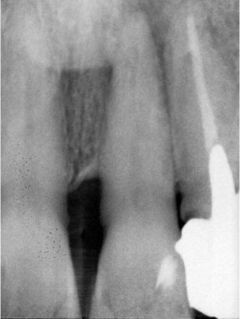

神経の治療

虫歯が大きく、神経が炎症を起こしてしまっていたり、根の先に膿が溜まってしまった場合などでも、可能な限り痛みを取り除き歯を保存していきます。

必要に応じて3Mix法も使用します。

抜髄(ばつずい)

感染根管治療(根尖病巣有)